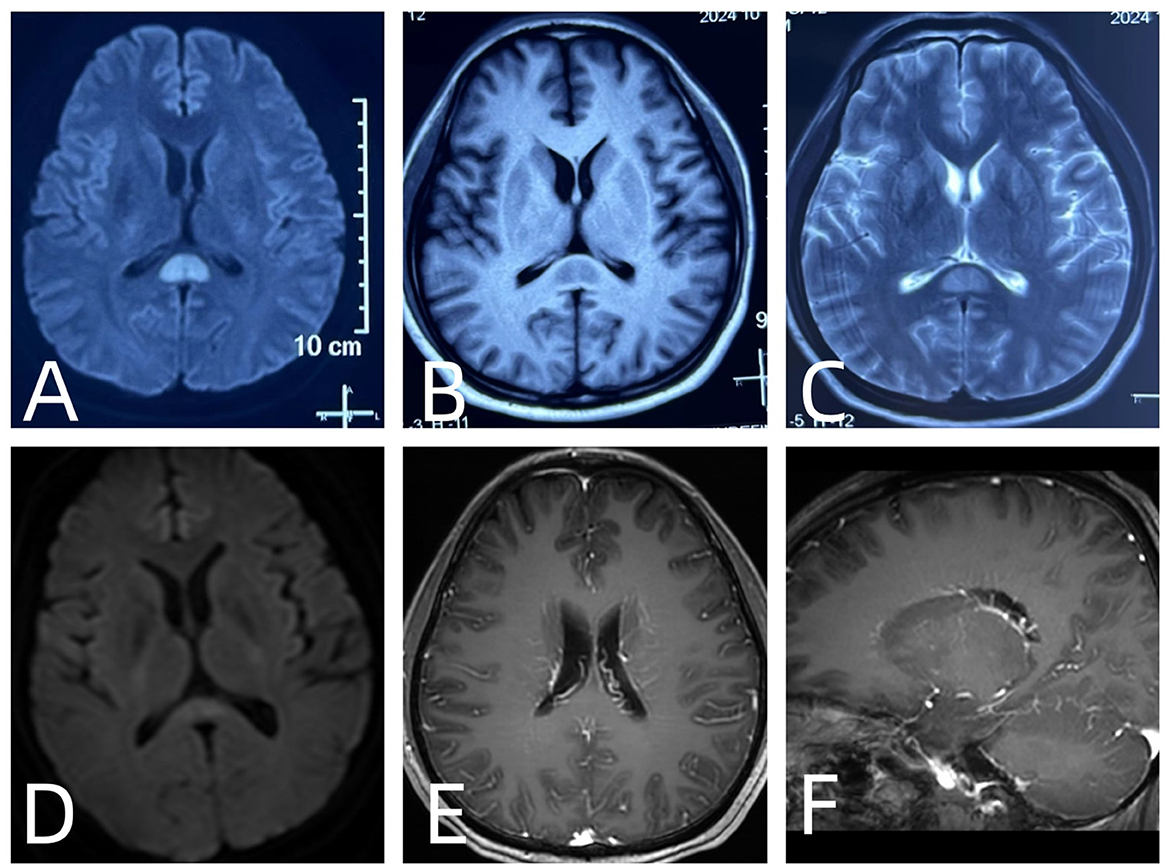

Brain MRI revealed RESLES-compatible abnormal signals in the SCC in all cases (Figure 1). Enhanced spinal MRI showed leptomeningeal enhancement in four cases (Figure 2). All patients received immunotherapy (corticosteroids, IVIG, or monoclonal antibodies), resulting in complete recovery in seven cases and neurological sequelae in five, with a maximum mRS score of 5.

Figure 1. (A) diffusion-weighted imaging (DWI): hyperintense signal in the splenium of the corpus callosum. (B) T1-weighted imaging (T1WI): hypointense signal in the splenium of the corpus callosum. (C) T2-weighted imaging (T2WI): hyperintense signal in the splenium of the corpus callosum. (D) Follow-up DWI: resolution of the previously observed hyperintense signal in the splenium of the corpus callosum. (E, F) Post-contrast imaging: linear perivascular enhancement radiating outward from the lateral ventricles.